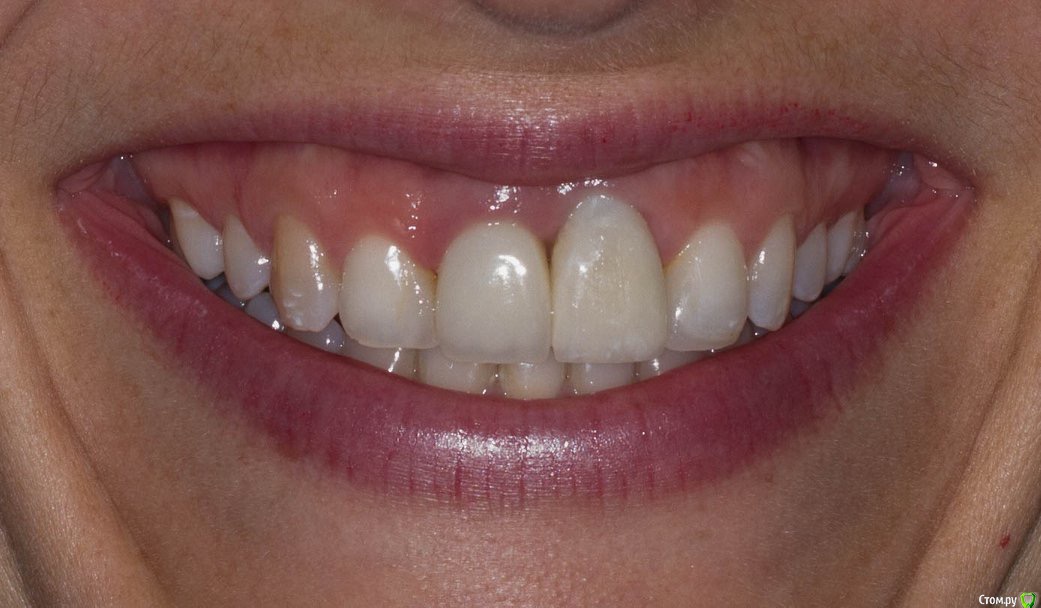

DenisV Опубликовано 21 марта, 2018 Поделиться Опубликовано 21 марта, 2018 Уважаемые коллеги планируется удаление и установка имплантата 3.8 10 dentium можно ли будет обойтись без костной и тканевой аугментации? Ссылка на комментарий

DenisV Опубликовано 21 марта, 2018 Автор Поделиться Опубликовано 21 марта, 2018 Уважаемые коллеги планируется удаление и установка имплантата 3.8 10 dentium можно ли будет обойтись без костной и тканевой аугментации? Ссылка на комментарий